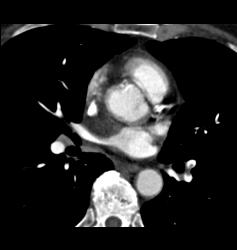

Pulmonary Embolism (PE) in Left Lobe Lung